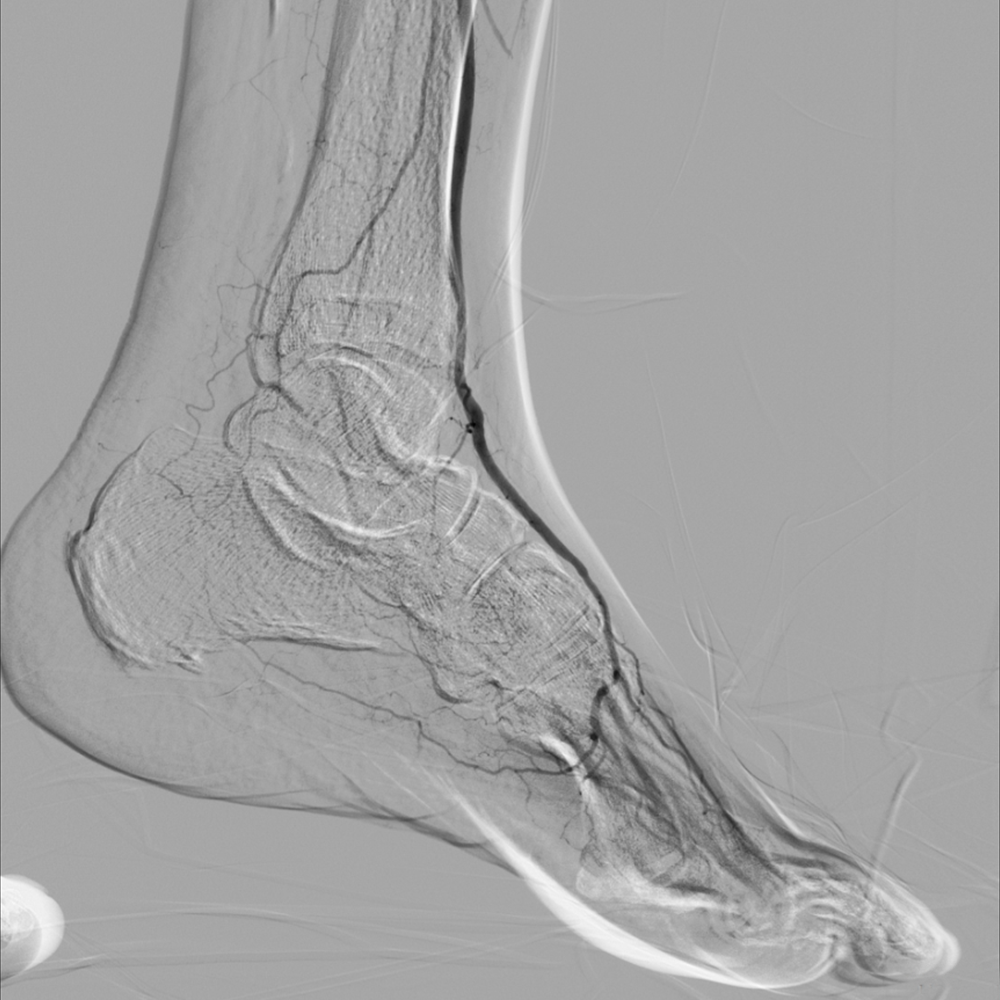

The pedal loop technique, allows for intervention on the distal tibial arteries and the pedal/plantar loop while only using one access site which can improve transcutaneous oxygen tension in the foot at 15 days.  The angiosome concept has gained popularity as an approach to improve limb salvage, whereby the target vessels for revascularization are chosen based on the angiosome in which the wound is located. The limb salvage was 86% when wound angiosomes were directly revascularized versus 69% for indirect revascuarlization.

Thus, a patent anterior tibial or posterior tibial artery in direct continuity with the foot and pedal arch would be chosen. The preferred conduit for Bypass surgery is Autogenous Vein graft (Saphenous vein)

Particularly in diabetic patients with leg ulcers or Gangrene, emphasize on the importance of restoring a pedal pulse and maximizing forefoot reperfusion adds tremendous value in maintaining graft patency and limb salvage.